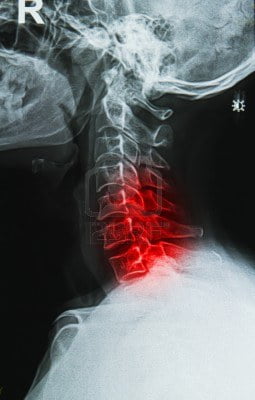

La prevención de accidentes en casa es esencial para salvaguardar la salud musculoesquelética y prevenir fracturas que pueden resultar de caídas u otros incidentes domésticos. Un traumatólogo en Monterrey brinda orientación especializada sobre cómo evitar situaciones peligrosas y crear un entorno doméstico más seguro.

A pesar de todos los esfuerzos de prevención, los accidentes pueden ocurrir. Si experimenta una caída o sufre una lesión en casa, es crucial consultar a un traumatólogo en Monterrey. La Clínica de Traumatología en Monterrey está dedicada a proporcionar asesoramiento y tratamiento especializado para lesiones musculoesqueléticas. No deje de priorizar su salud y consulte a un traumatólogo en Monterrey para obtener orientación experta y cuidado de calidad. Su bienestar está en manos capacitadas.